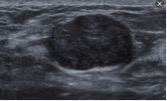

- Ultrasonografi (USG) Payudara - akan menunjukkan bentuk oval margin padat dengan baik